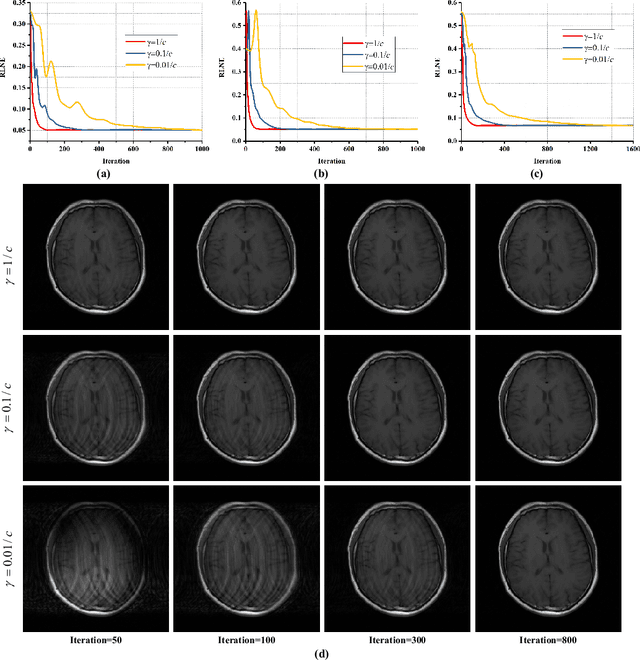

Abstract:Magnetic Resonance (MR) Fingerprinting is an emerging multi-parametric quantitative MR imaging technique, for which image reconstruction methods utilizing low-rank and subspace constraints have achieved state-of-the-art performance. However, this class of methods often suffers from an ill-conditioned model-fitting issue, which degrades the performance as the data acquisition lengths become short and/or the signal-to-noise ratio becomes low. To address this problem, we present a new image reconstruction method for MR Fingerprinting, integrating low-rank and subspace modeling with a deep generative prior. Specifically, the proposed method captures the strong spatiotemporal correlation of contrast-weighted time-series images in MR Fingerprinting via a low-rank factorization. Further, it utilizes an untrained convolutional generative neural network to represent the spatial subspace of the low-rank model, while estimating the temporal subspace of the model from simulated magnetization evolutions generated based on spin physics. Here the architecture of the generative neural network serves as an effective regularizer for the ill-conditioned inverse problem without additional spatial training data that are often expensive to acquire. The proposed formulation results in a non-convex optimization problem, for which we develop an algorithm based on variable splitting and alternating direction method of multipliers.We evaluate the performance of the proposed method with numerical simulations and in vivo experiments and demonstrate that the proposed method outperforms the state-of-the-art low-rank and subspace reconstruction.